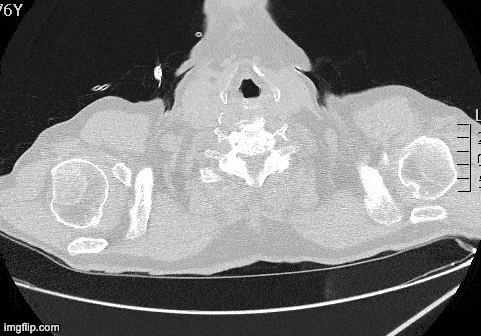

Chest CT Findings in COVID-19 In a study by Ai et al (n=1014), chest CT was compared to RT-PCR for the diagnosis of COVID-19. Characteristic findings on CT included ground-glass opacities, multifocal patchy consolidation, and/or interstitial changes with a peripheral distribution. In patients with a positive RT-PCR, characteristic findings on chest CT demonstrated a sensitivity of 97% and specificity of 25%. In a small subset of patients with serial RT-PCR performed (initial negative followed by positive result) a positive chest CT was present PRIOR to the positive RT-PCR. Link Image Courtesy of Dr. Marco Garrone (@drmarcogarrone)